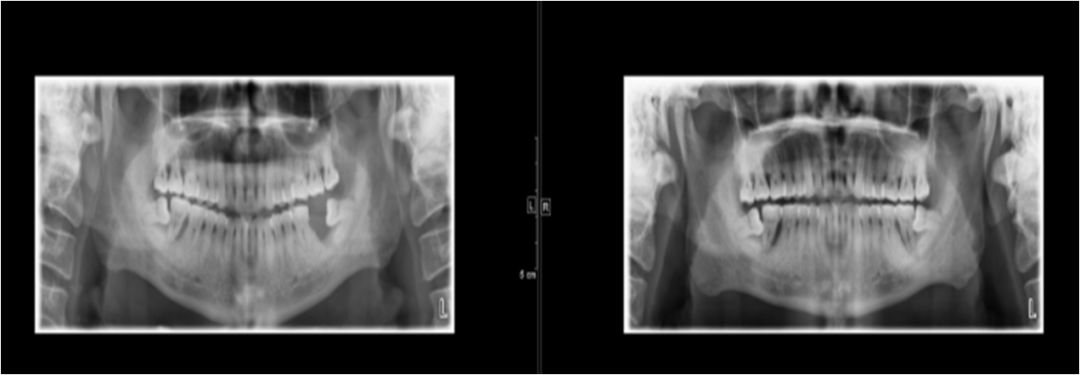

04 咀嚼肌间隙、颌下间隙、左侧颞下间隙,颊间隙,翼颌间隙

男,55岁,左下后牙反复肿疼1年余,加重1月余,疼痛剧烈伴张口受限,面部肿胀。

咀嚼肌间隙有脓肿形成。